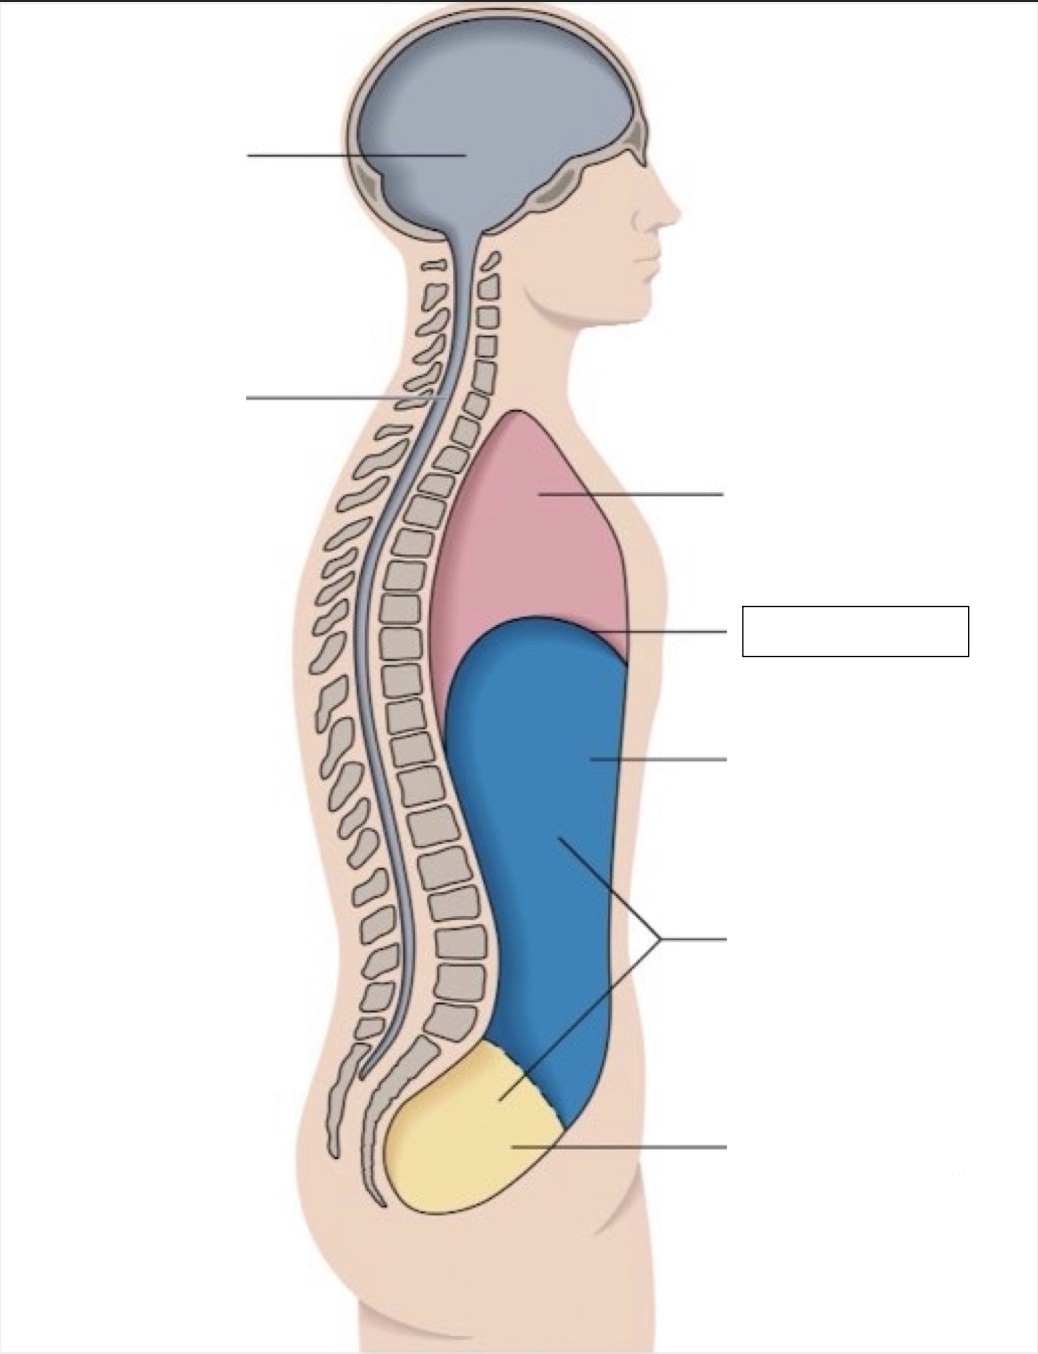

thoracic cavity

diaphragm

abdominal cavity

abdomino-pelvic cavity

pelvic cavity

spinal cavity

cranial cavity